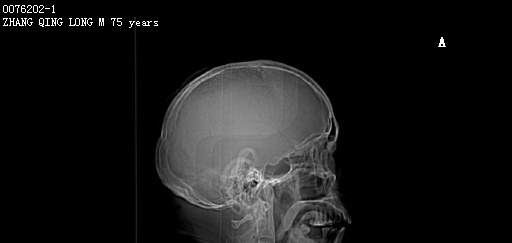

CT50996:M,74y。头痛伴左上肢无力2天。

男,74岁。头痛伴左上肢无力2天。 既往史:发现前列腺占位1月余。 PE:左上肢肌力下降。 临床诊断:头痛原因待查。 今行头部CT扫描,图像如下: ...

左侧顶枕叶可见团块状密度高低不均影,内见钙化,局部颅板受侵,考虑脑转移瘤并瘤卒中可能性大。

颅骨有增厚及骨质破坏,应该是脑膜瘤可能大。

考虑前列腺癌脑转移,{高密度,无水肿,脑膜转移}

考虑左侧顶部颅内脑外占位(脑膜转移瘤并肿瘤卒中?);建议行CT增强扫描或MRI检查。

密度高,有钙化,符合前列腺癌转移瘤特点。

左侧顶部可见类圆形高密度影,内似见钙化灶,占位效应较轻,未见明确水肿。

个人觉得不支持转移,瘤卒中不除外,建议MR增强。